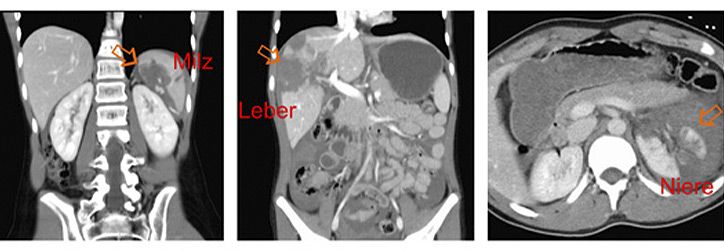

Die Bauchorgane werden in Europa fast ausschließlich durch stumpfe Traumen verletzt. Die Unfallursachen sind altersabhängig und bei Kleinkindern v.a. Stürze, bei Schulkindern zunehmend Sportunfälle und in allen Altersgruppen Verkehrunfälle. Am häufigsten sind Milz, Leber und Nieren (Abbildung) verletzt, seltener die Bauchspeicheldrüse oder der Magen-Darm-Trakt.